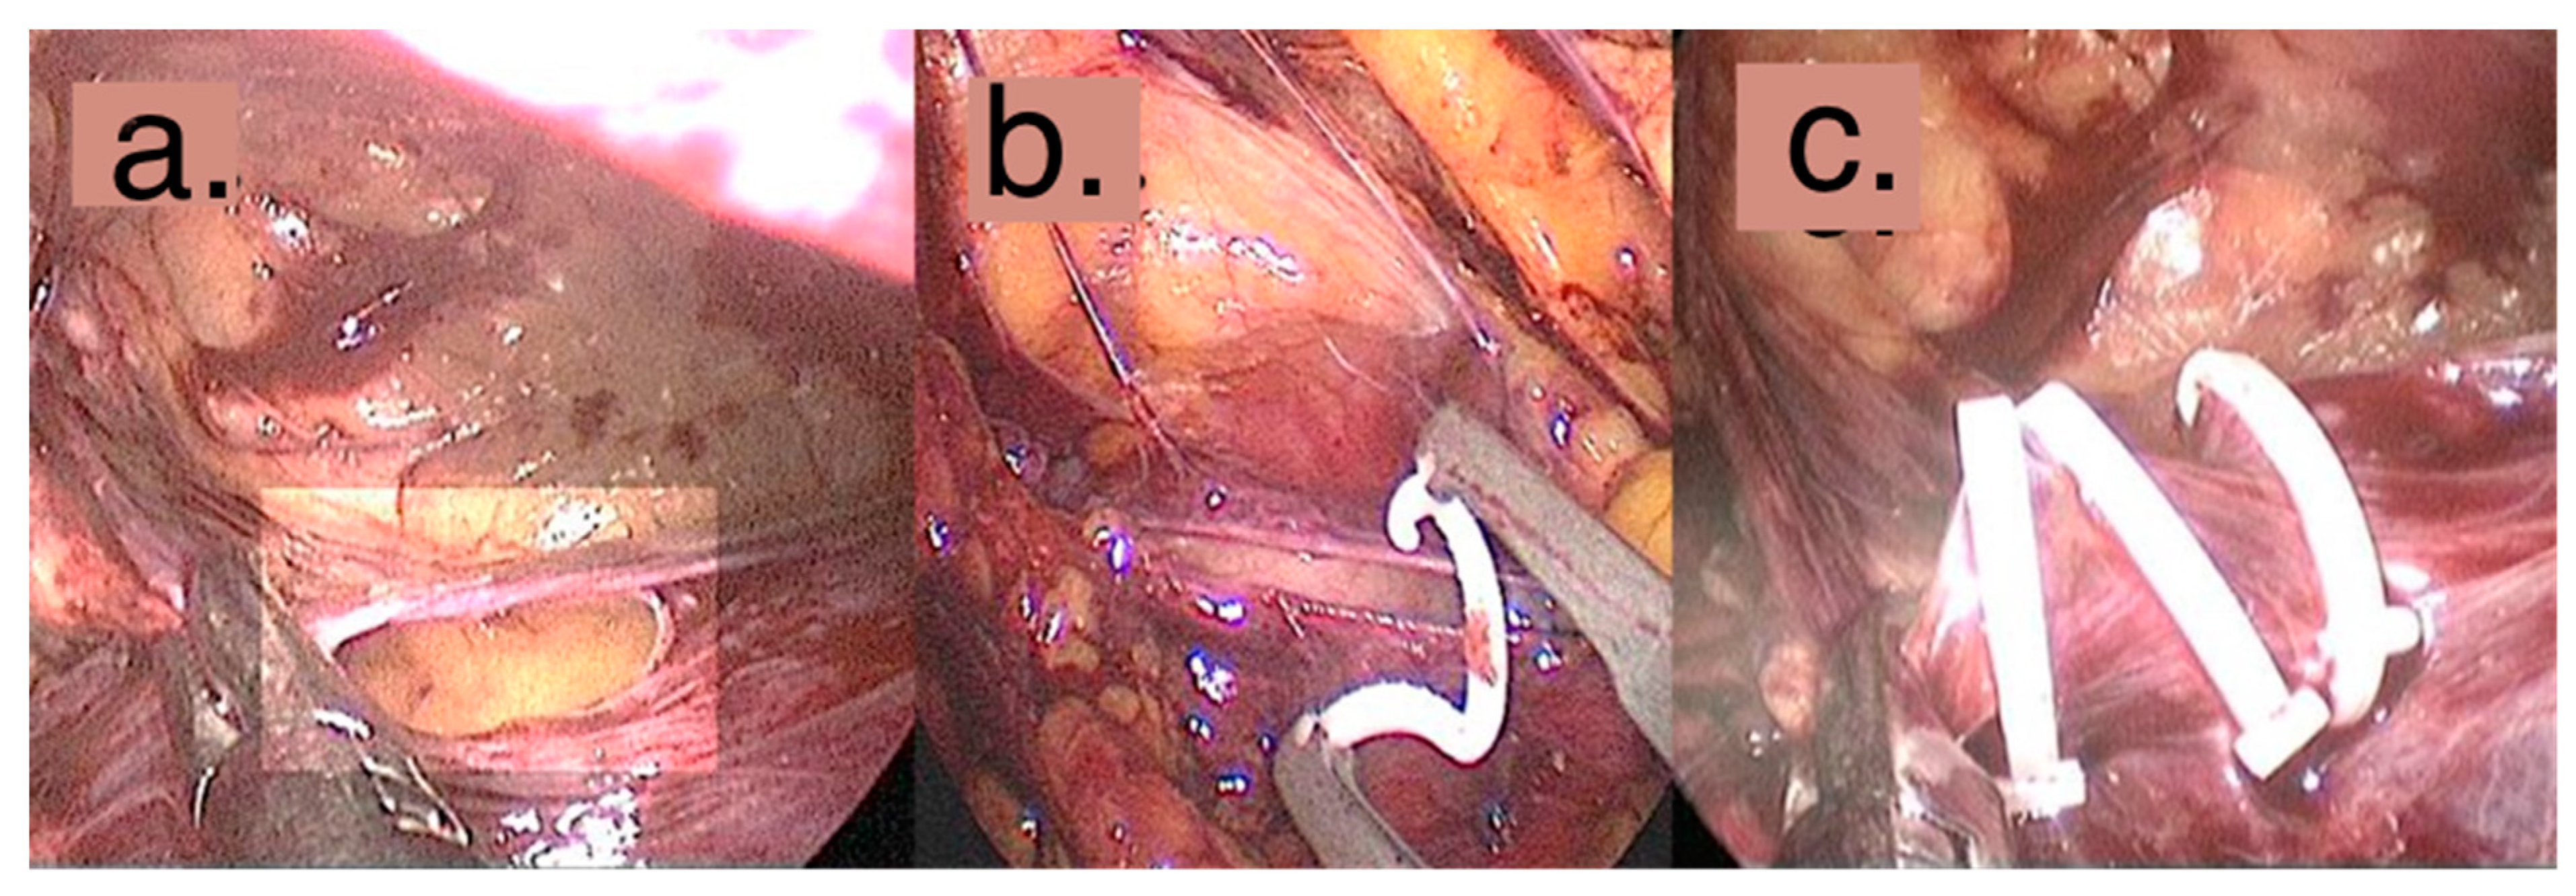

2.1. Surgical Technique